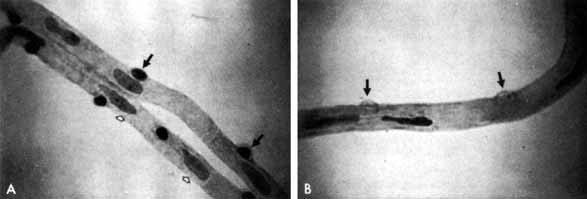

EARLY NONPROLIFERATIVE DIABETIC RETINOPATHY

Although microaneurysms are the first ophthalmoscopically detectable change in diabetic retinopathy, the earliest abnormalities seen histopathologically are thickening of the capillary basement membrane1,2 and pericyte dropout.3,4 Pericytes are mesothelial cells that surround and support the retinal capillary endothelial cells. Normally there is one pericyte per endothelial cell. In people with diabetes, however, the pericytes die off and are decreased in number (Fig. 1). Their absence weakens the capillaries and permits thin-walled dilatations, called microaneurysms, to develop. Later, endothelial cells proliferate and lay down layers of basement membrane material. Fibrin may accumulate within the microaneurysm along with erythrocytes, and the lumen of the microaneurysm may become occluded (Fig. 2). Initially, most microaneurysms are on the venous side of the capillaries, but later they are seen on the arterial side as well. Clinically, they appear as small red dots (Fig. 3). Despite the multiple layers of basement membrane, microaneurysms are permeable to water and large molecules, allowing the transudation of fluid and lipid into the retina.

Fig. 2 Trypsin digest preparation of early background retinopathy. Early microaneurysm (closed arrow), aneurysm with endothelial proliferation (open arrow), and aneurysm occluded with fibrin (curved arrow). (Courtesy of Dr. Myron Yanoff)